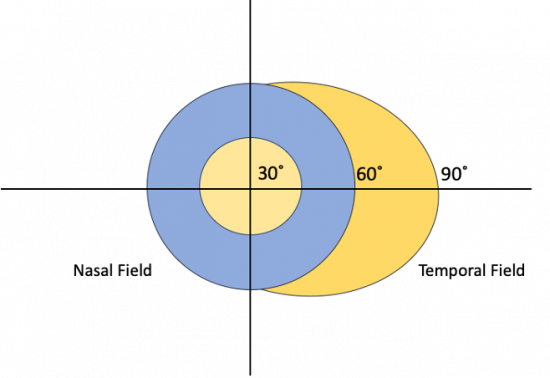

The etiology for this special monocular visual field defect is due to the distribution and overlap of the nasal and temporal visual fields. The normal visual field in degrees from the central point is 60 degrees nasal, 50 degrees superiorly, and 90-100 degrees temporally (Figure 1). The nasal and temporal hemifields in each eye overlap but the monocular temporal crescent has no perimetric correlate in the fellow eye because the temporal visual field is larger than the nasal visual field, hence there are more crossing nasal fibers than there are ipsilateral temporal fibers with a 53:47 ratio. [2] The extra nasal fibers that cross accounts for the non-overlapping contralateral temporal crescent. These fibers end up in the most anterior medial striate cortex and compromise 8-10% of the striate cortex. [3] This monocular representation in a retrochiasmal pathology is attributed to the monocular innervation in that area.[4] Thus, 30-40 degrees of the peripheral temporal visual field is unpaired and has unilateral representation in the contralateral visual cortex. Damage to this area of the visual cortex leads to the contralateral temporal crescent (Figure 2.)[5][6]